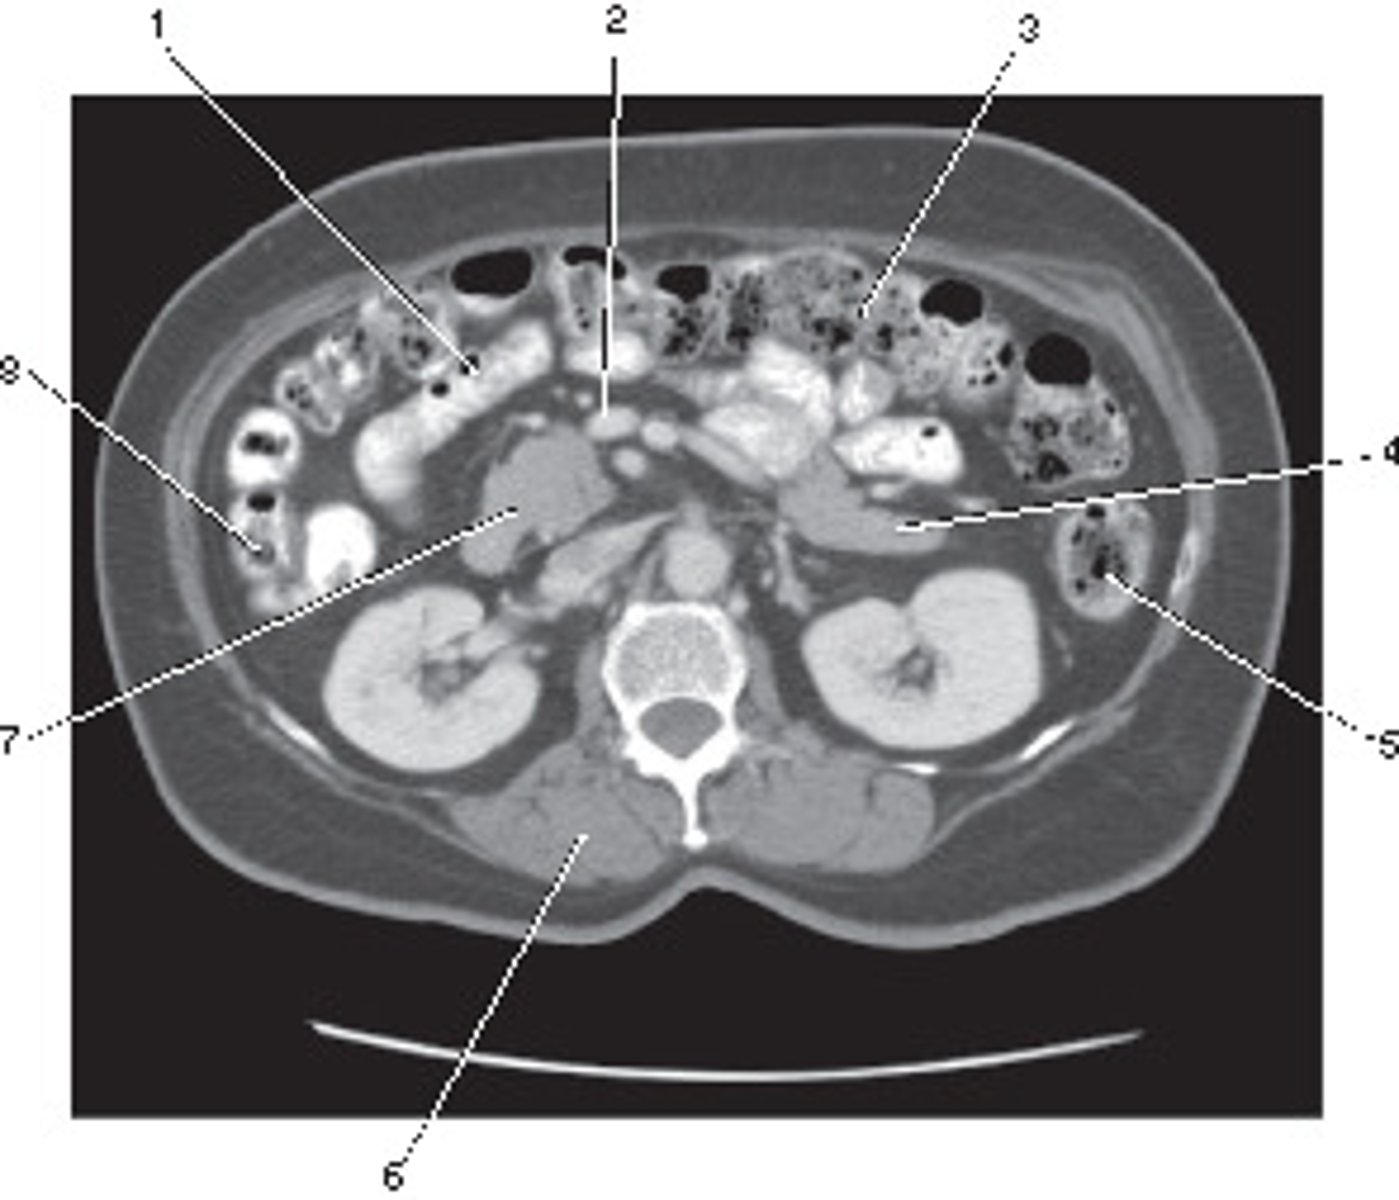

Corticomedullary;

30-40 seconds after injection,

the corticomedullary phase demonstrates optimal enhancement of the renal cortex with maximum differentiation from the renal medulla

This image of the abdomen was most likely acquired in which in which renal enhancement phase?

<p>This image of the abdomen was most likely acquired in which in which renal enhancement phase?</p>

Renal Cortex

Number 1 corresponds to which of the following?

<p>Number 1 corresponds to which of the following?</p>